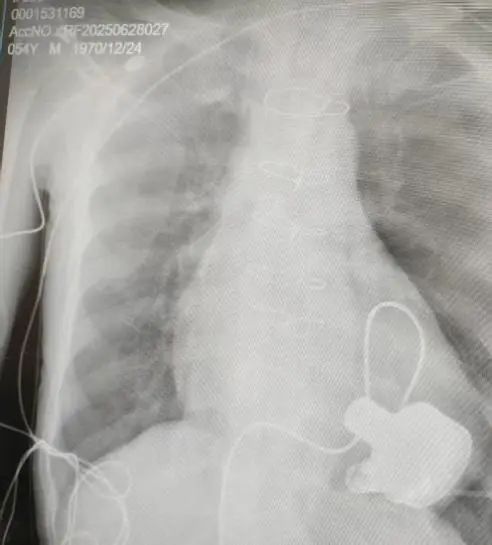

术后影像